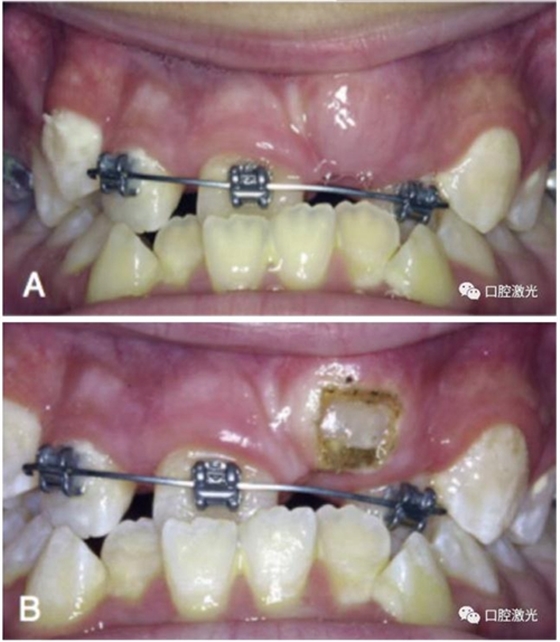

有時,會遇到一些口腔衛(wèi)生問題比較嚴重的患者,從而導(dǎo)致牙齦發(fā)炎而腫大。通過改善口腔衛(wèi)生環(huán)境,炎癥可以得到緩解,但增生的牙齦不一定都可以完全恢復(fù)。下圖的患者就存在口腔牙齦肥厚問題,同時左上部犬牙存在部分萌出的問題,右上部犬牙存在未萌出問題,這些問題都妨礙了托槽的粘接。因此,實施了全口腔的牙齦整形手術(shù)。去除了多余的牙齦組織,增加了犬牙的暴露面積,從而使托槽的粘接更為便利,同時也提升了患者保持口腔衛(wèi)生的狀況。

治療前

激光牙齦整形后即刻

激光治療當(dāng)天粘接托槽

6周后效果